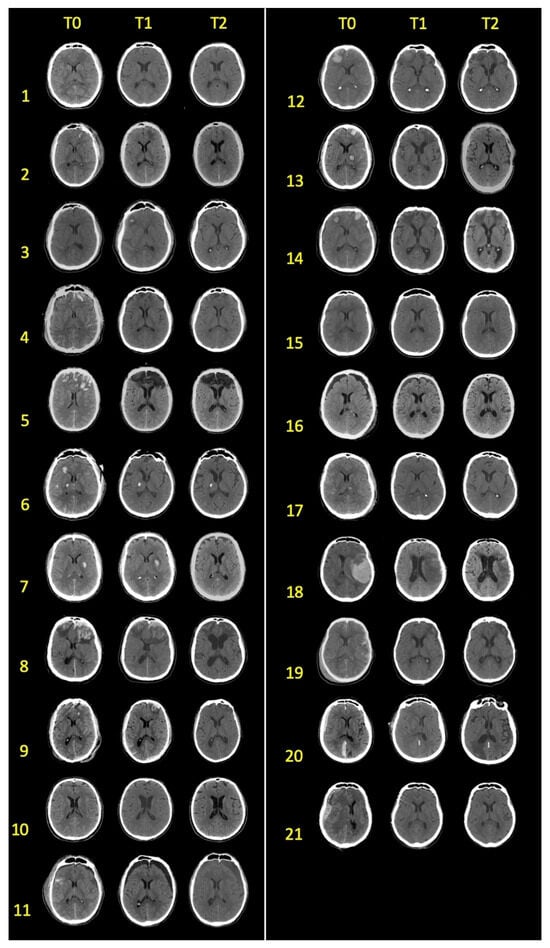

2.2. CT Brain Images

2.4. Brain Damage Evaluation